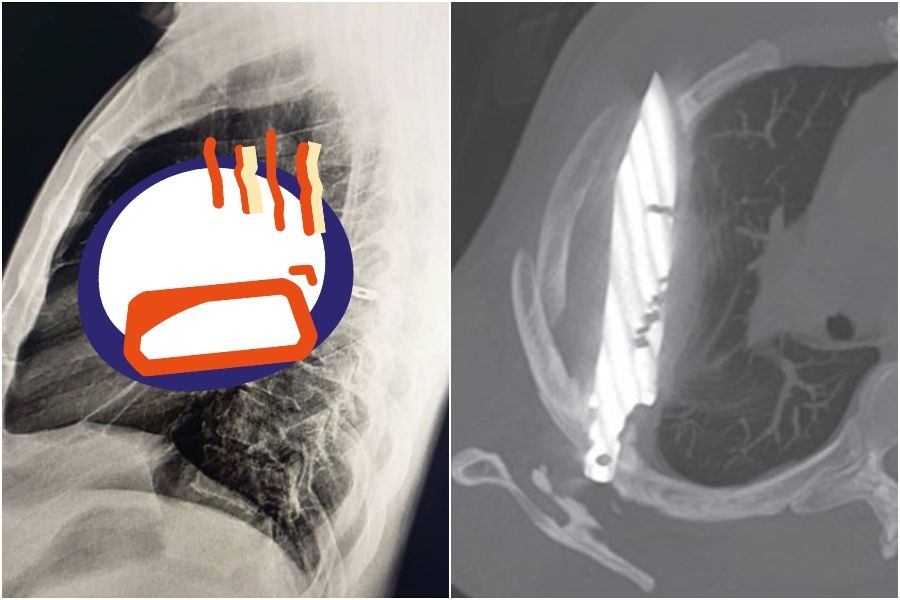

▲ 男子胸腔插著一把刀長達8年。(圖/翻攝自Journal of Surgical Case Reports)

胸部X光檢查揭開謎底,影像清楚顯示有一把刀埋在患者胸腔內,神奇的是這把刀從右肩胛

骨刺入,奇蹟般避開所有重要器官。